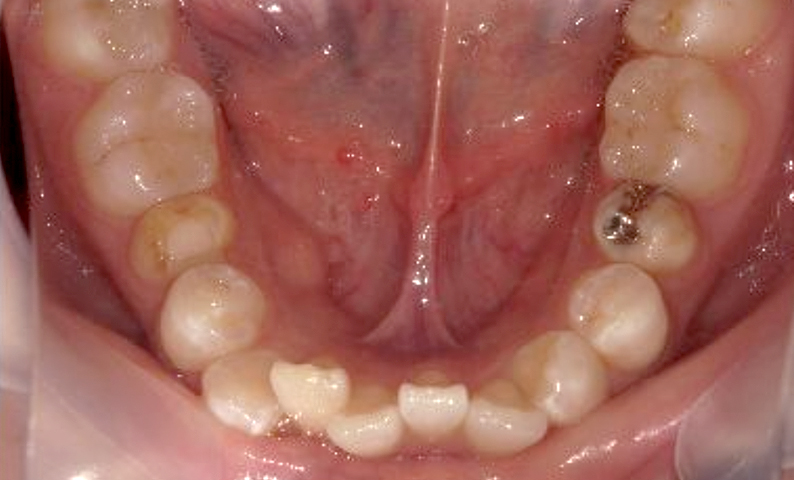

症例_001 下顎だけの部分矯正

治療期間:6ヶ月金額:27万円+税女性前歯のガタガタ下の前歯だけ

| Before | After |

|---|---|

|